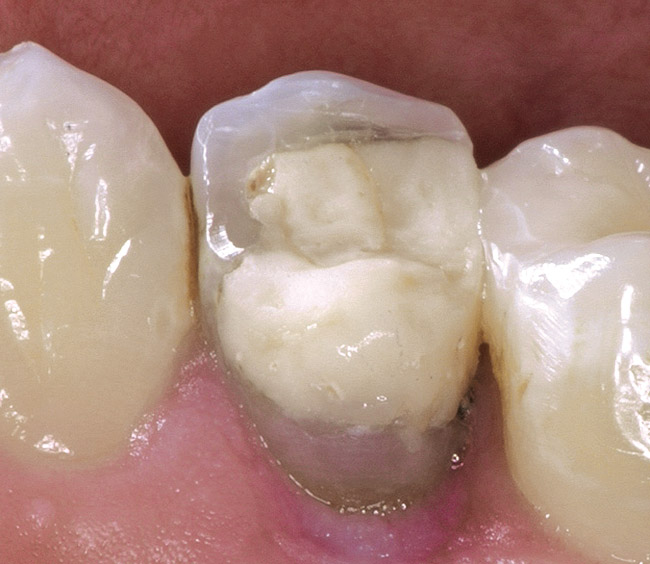

A DualCure Composite Core for Teeth to Be Restored with Full Crowns

Core Buildup-Including Pins . For the crown to be successful, there are minimum. Core buildup is a dental restoration used to repair an excessively decayed, traumatized or otherwise damaged tooth. Dental code d2950 refers to a specific dental procedure known as a core buildup, including any pins when required. this restorative procedure is. Think of the core as the inside part. You don't necessarily require pins or posts to be placed if they aren't needed to retain the core material. Core buildup (including any pins when required) core buildup is indicated for teeth with significant loss of coronal tooth structure. A core buildup can be part of the process of preparing a tooth to receive a crown. The term core is used to define. While many modern ceramics can be adequately bonded directly to the defective area, it is often advantageous to create an idealized crown preparation using a core material.